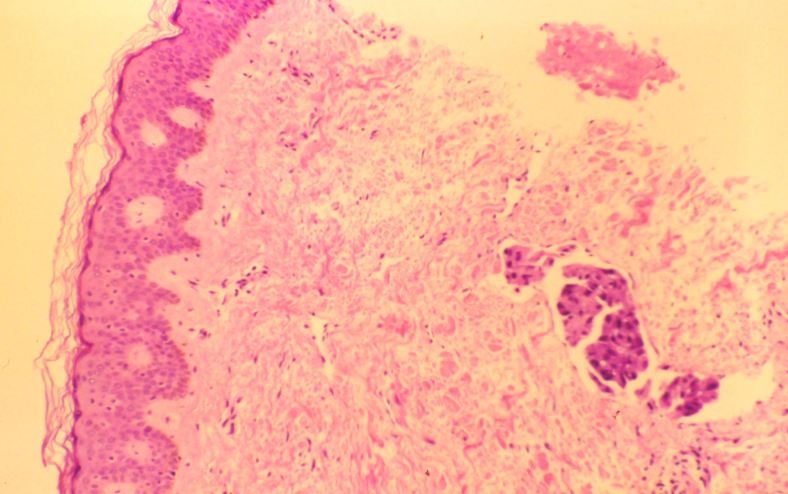

Skin punch biopsy — skin surface to the left, with a focus of dermal lymphatic invasion on the right. This finding on pathology is not a requirement for the “inflammatory” designation, but is frequently present.